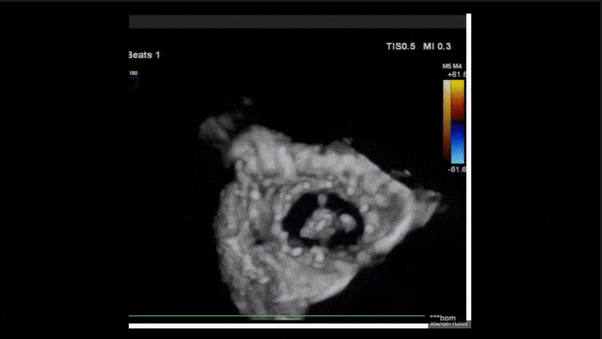

術(shù)后即刻返流

術(shù)后即刻返流三維

術(shù)中經(jīng)食道超聲輔助下可見LuX-Valve Plus夾持件抓捕瓣葉狀態(tài)良好,夾持件在位,室間隔錨定位置良好,假體瓣膜整體錨定狀態(tài)穩(wěn)固。

術(shù)后三維超聲

術(shù)后即刻經(jīng)食道超聲可見,三尖瓣假體瓣膜位置合適,牛心包瓣葉運(yùn)動狀態(tài)良好,開閉正常,瓣周及瓣葉對合緣處未見明顯返流,心電圖及心包狀態(tài)較術(shù)前無明顯變化。